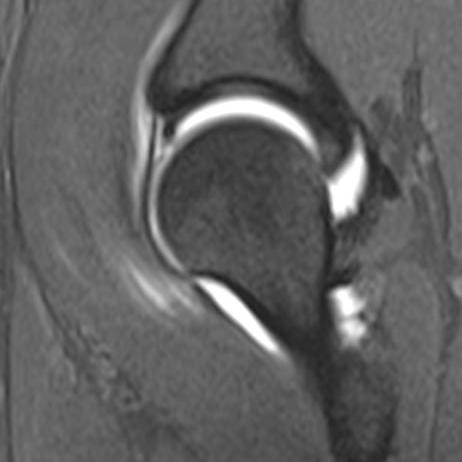

Die MRT ist inzwischen unverzichtbarer Bestandteil der Diagnostik am Bewegungsapparat. Muskeln, Sehnen, Bänder, Knochen und Knorpel, sowie deren Krankheitszustände lassen sich in unvergleichlicher Weise differenzieren. Einige Krankheitsbilder wie z.B. das "traumatische Knochenödem" oder die knöcherne Stressreaktion sind überhaupt erst durch die MRT bekannt geworden.